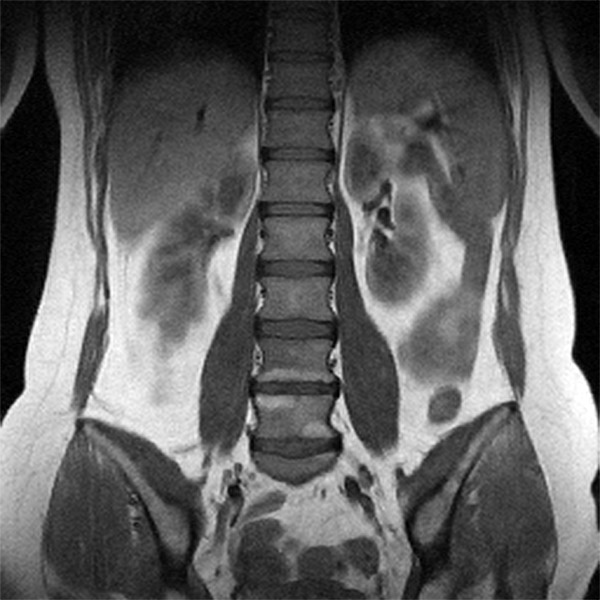

Мрт картина дегенеративно дистрофических изменений пояснично крестцового отдела позвоночника